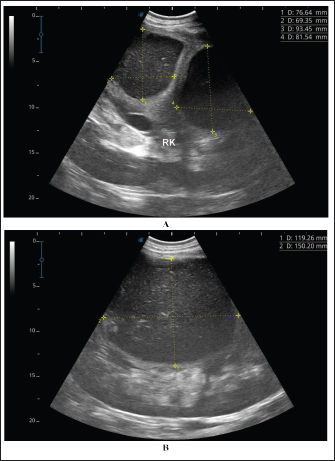

Ultrasonographic findings in camel number 9 with right kidney abscesses are shown in Figure 7, where the lesion appeared compressing the parenchyma of the right kidney. Its contents are hyperechoic, and its capsule is thick. Figure 8 shows sonographic findings in camel number 11 with abscessation of the right and left kidneys. Abscesses measured 7.6 × 6.9 cm and 9.3 × 8.1 cm with isoechoic contents. A third abscess in the same camel was found within the left kidney. It was relatively large and was isoechoic. Ultrasonographic findings in camels 15 and 16 with abscesses of the left kidney are shown in Figure 9. A large abscess was found in camel number 15 with isoechoic contents and a thick capsule, while a small abscess was imaged in the left kidney of animal number 16 with heterogeneous contents. Figure 10 shows the ultrasonographic findings in camel number 17 with abscessation of the left kidney. A large abscess was found compressing the parenchyma of the left kidney with isoechoic contents. The urinary bladder in the same camel contained echogenic deposits that appeared to be highly echogenic.

Fig. 8. Ultrasonographic findings in camel number 11 with right and left kidneys. Image A shows 2 abscesses within the right kidney (RK) and measuring 7.6 × 6.9 cm and 9.3 × 8.1 cm with isoechoic contents. Image B shows a relatively large abscess in the left kidney, and measuring 11.9 × 15.0 cm and with isoechoic contents.